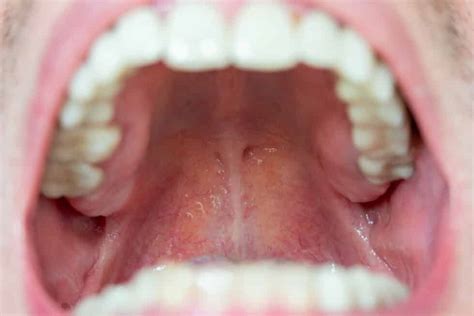

El paladar, la parte superior de la boca, es esencial para masticar, tragar y hablar. Aunque no se suele hablar de él, la inflamación del paladar puede ser dolorosa e incómoda. Esta condición, conocida como paladar inflamado, puede tener diversas causas. En este artículo, exploraremos las razones más comunes por las que se inflama el paladar, cómo identificar los síntomas y qué tratamientos están disponibles.

La mayoría de las afecciones o lesiones que afectan al paladar no suelen ser peligrosas ni complicadas de tratar. A continuación, se detallan algunas de las causas más comunes:

Una de las causas más frecuentes de la inflamación del paladar son las agresiones externas causadas por quemaduras o irritaciones. Al consumir alimentos muy calientes o picantes, se puede causar inflamación, así como elementos duros o crujientes que rompen o hieren la zona. Ante una irritación o quemadura, el paladar se volverá de un color rojizo o rosa intenso y mostrará sensibilidad. Para sanar el paladar por quemadura es recomendable utilizar enjuague bucal y esperar al menos una semana a que desaparezca.

Las aftas o úlceras bucales son inflamaciones o bultos que se producen en la mucosa de la boca. Muestran una forma redondeada y un color blanquecino, son dolorosas y producen molestias al masticar. Este tipo de úlceras puede generarse por deficiencia de vitaminas, heridas previas en la mucosa bucal, problemas con el sistema inmune o sin ninguna razón aparente.